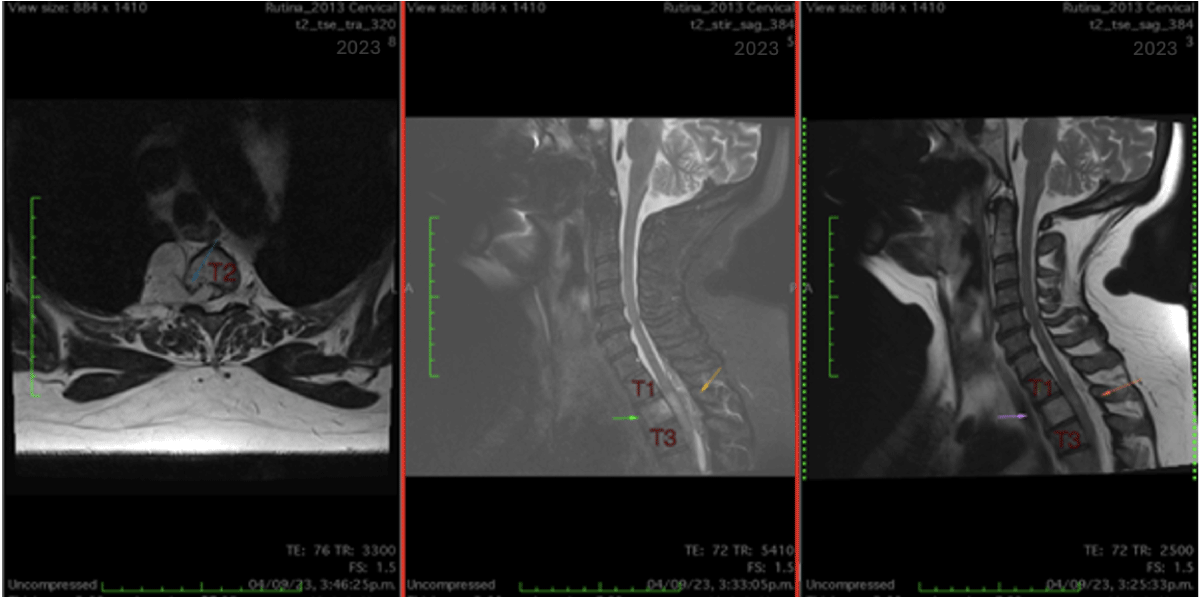

Preoperative MRI imaging of thoracic spinal tumor

Figure 1: Thoracic spine MRI. A) Axial projection in T2-sequence: Intradural-extramedullary expansive mass, hyperintensity compared to the surrounding spinal cord. B) Sagittal projection in T2-sequence: Intradural-extramedullary mass in the upper thoracic region compressing the spinal cord and displacing the surrounding structures. C) Sagittal projection in T2-sequence with fat suppression and contrast: Highlighting the expansive intradural-extramedullary lesion at the mid-thoracic level, with enhancement after contrast administration.

Figure 1: Thoracic spine MRI. A) Axial projection in T2-sequence: Intradural-extramedullary expansive mass at the thoracic level, which shows hyperintensity compared to the surrounding spinal cord; B) Sagittal projection in T2-sequence: Intradural-extramedullary mass in the upper thoracic region compressing the spinal cord; C) Sagittal projection in T2-sequence with fat suppression and contrast: Highlighting the expansive intradural-extramedullary lesion at the mid-thoracic level, with enhancement after contrast administration. View Figure 1